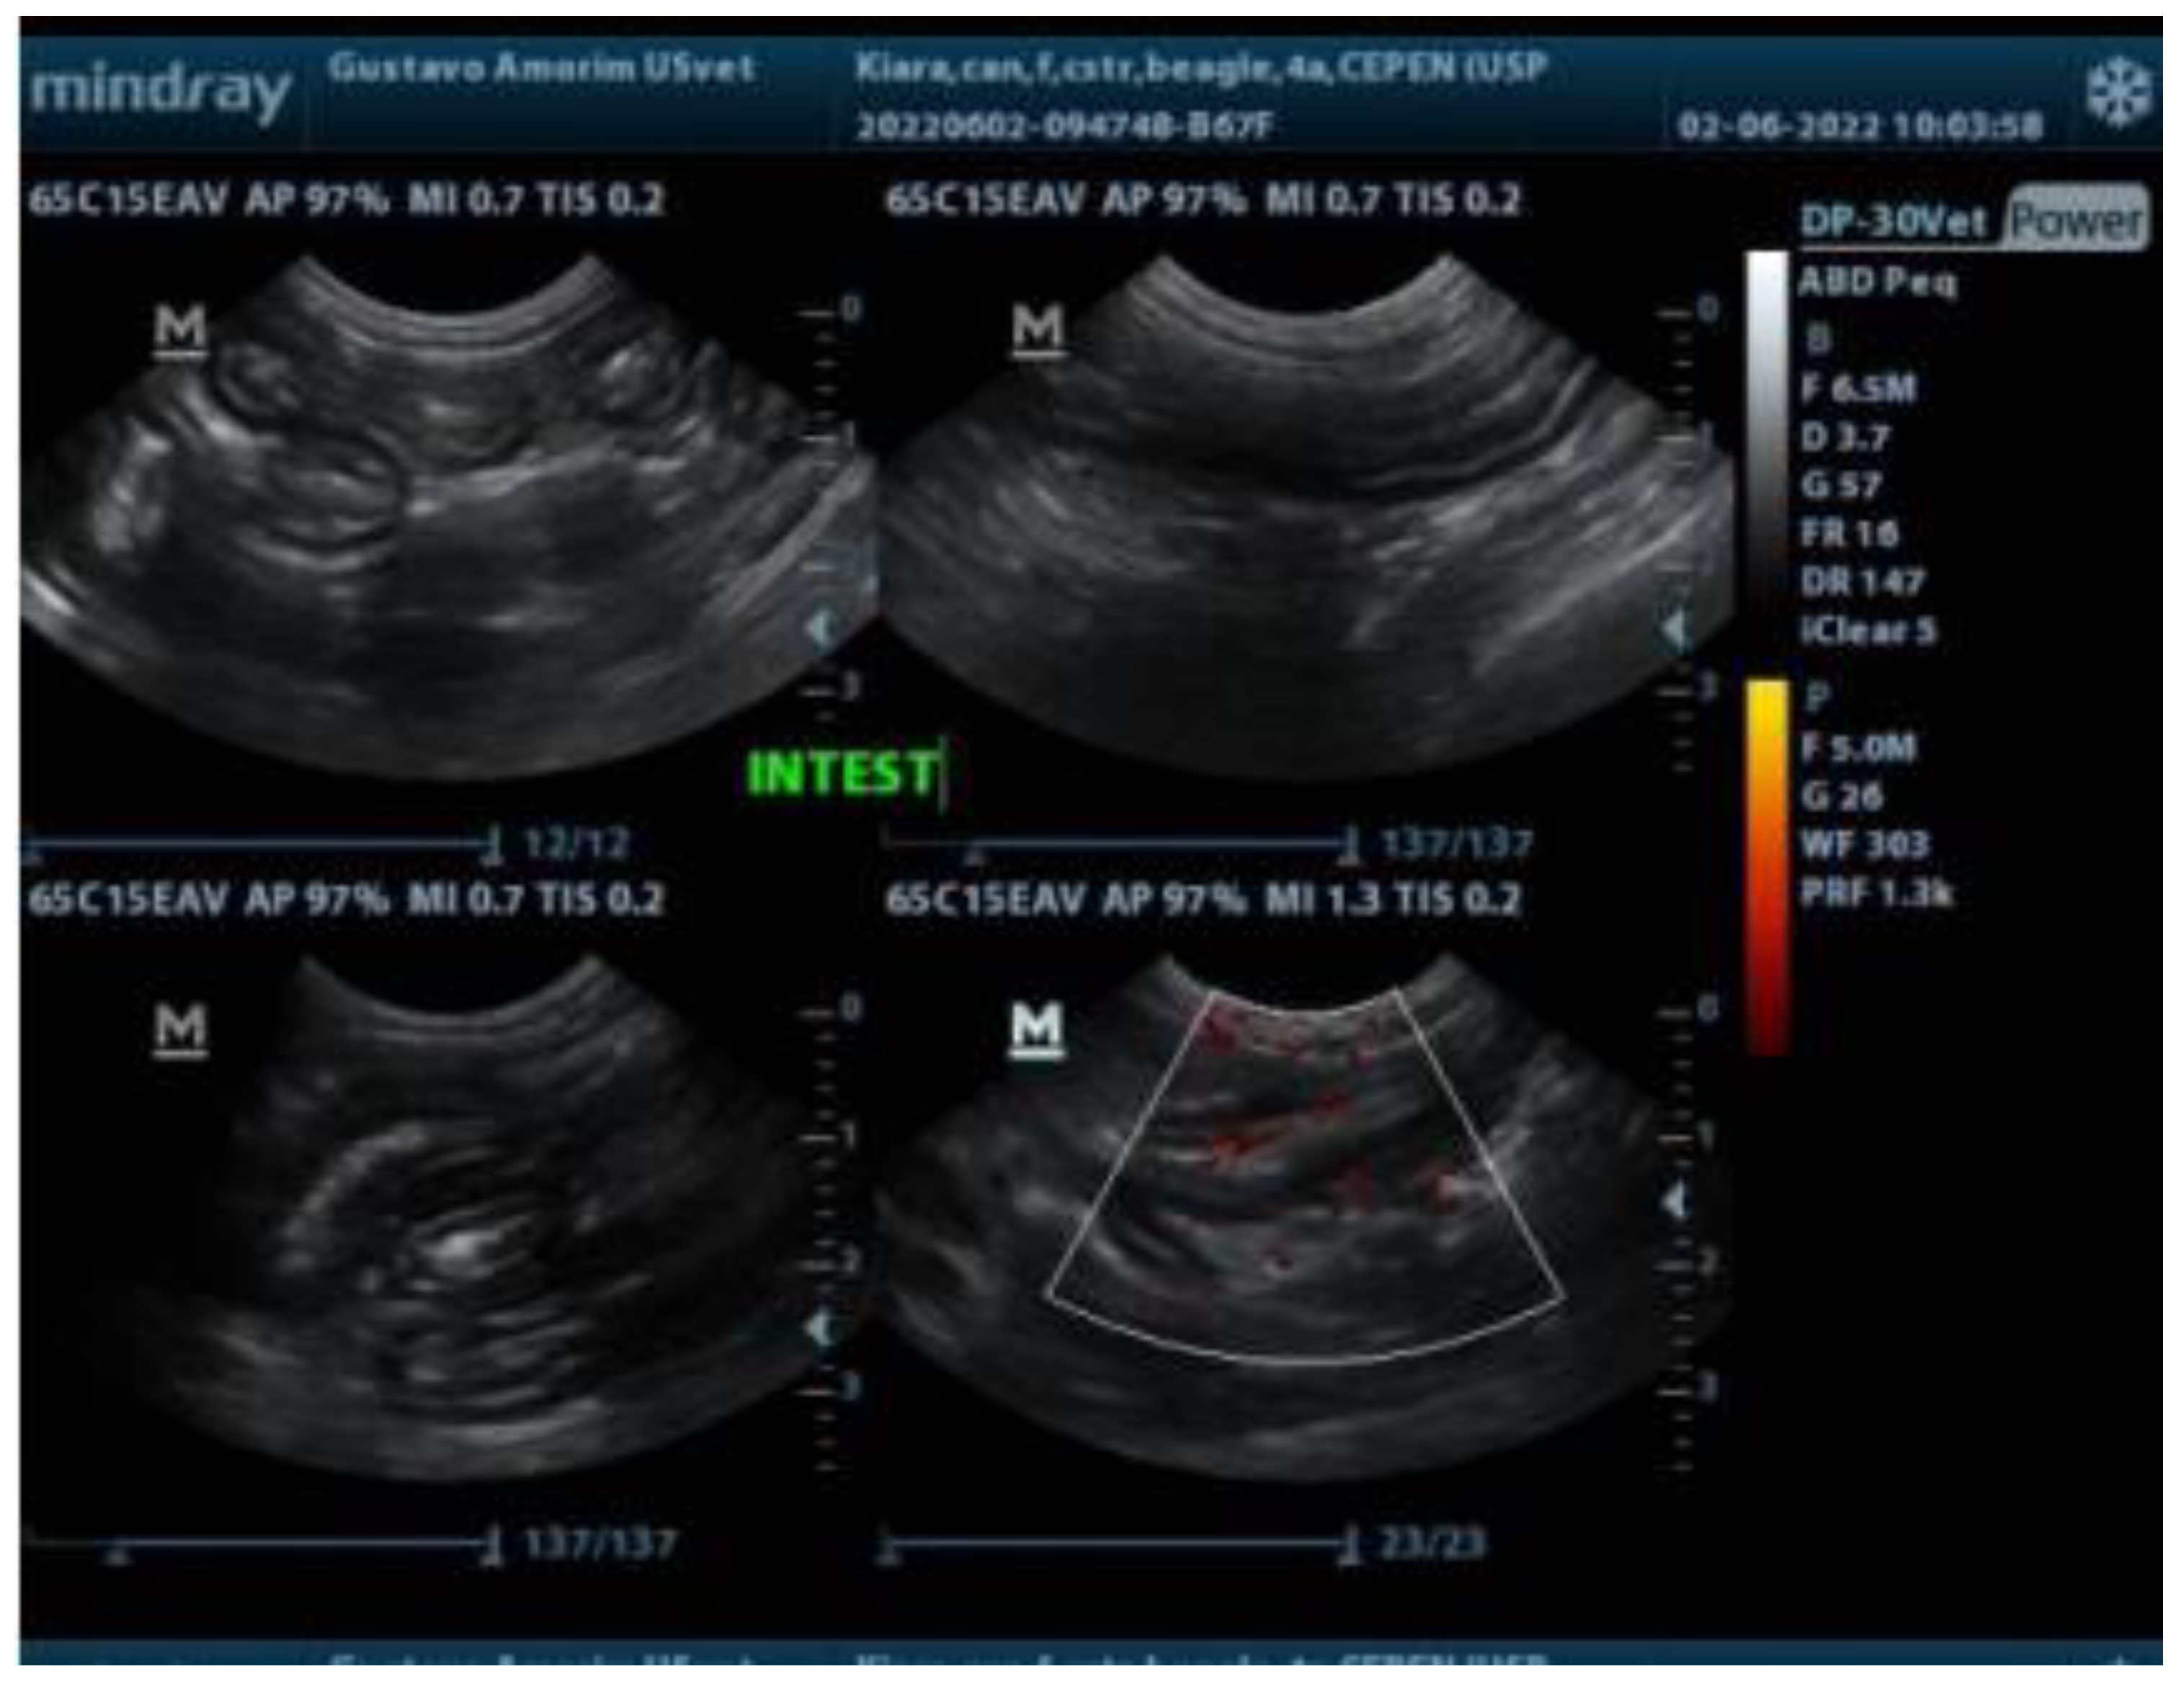

3. Case Report